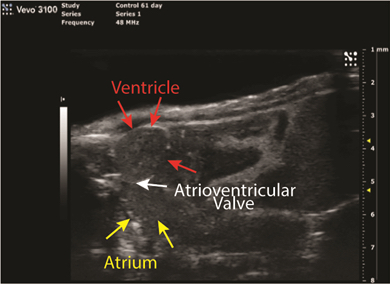

Rat left ventricle apex — tissue Doppler. Courtesy of Dr. Lynn Weber, WCVM.